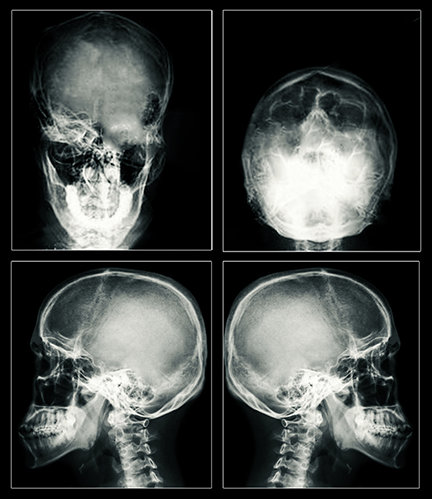

Το αποτέλεσμα παραμένει το ίδιο: μια τονικοκλονική κρίση και βλάβη στον εγκέφαλο, η οποία μπορεί να είναι μόνιμη. Σήμερα η μεγάλη αύξηση της ροής του ρεύματος μπορεί να ανοίξει τρύπες στα εγκεφαλικά κύτταρα, σκοτώνοντας τα κύτταρα. Η ηλεκτρική ενέργεια μπορεί επίσης να σκοτώσει τα κύτταρα παράγοντας θερμότητα. Οι μαγνητικές τομογραφίες ασθενών του ECT έχουν δείξει ουλές και συρρίκνωση του εγκεφάλου – αδιαμφισβήτητη απόδειξη σοβαρής βλάβης.